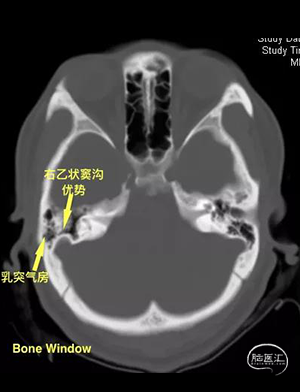

头颅CT(2021-09-14),术前阅片,手术预判。